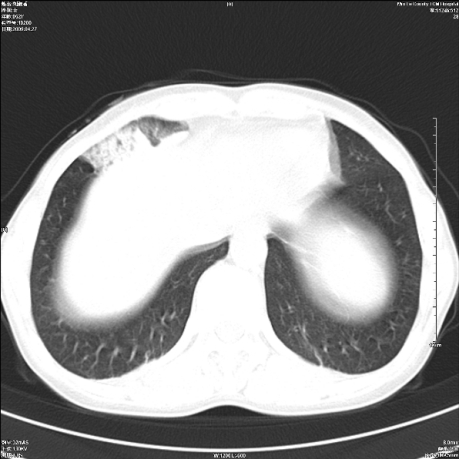

标题: CT19625:女52间断性喀血 [打印本页]

标题: CT19625:女52间断性喀血

考虑右肺中叶感染性病变并右肺中、下叶肺泡积血;建议抗炎、止血治疗后复查。

右肺中叶炎症;右肺中、下叶肺泡积血

右肺中叶支气管扩张并感染或咳血沉积,块右肺中下叶肺泡积血。

右肺中叶慢性炎症伴局部支扩并中下叶肺泡积血。

考虑右肺中叶感染性病变并右肺中、下叶肺泡积血。建议治疗后复查。